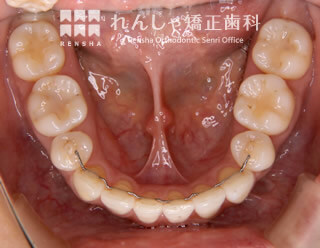

叢生(20歳 治療期間:2年6か月)

上下前歯のがたつきの原因は、歯とアゴの大きさの不調和です。顎を大きくできない場合は歯の本数を減らすことになります。

綺麗に並んだ歯並びも長期間維持できなければ意味がありません。そのために保定装置(マウスピース)のご協力をお願いしています。

| 主訴 | 前歯のがたつき |

|---|---|

| 診断名 | Angle Class I 叢生 |

| 初診時年齢 | 20歳2か月 |

| 装置名 | マルチブラケット装置 |

| 抜歯非抜歯 | 上下顎左右第一小臼歯の抜歯(合計4本) |

| 治療期間 | 2年6か月 |

| 費用の目安 | 約89万円+消費税(検査料金、都度の処置費用等も合わせた総額) |

| リスク副作用 | 歯の移動に伴う軽微な歯根吸収、歯槽骨吸収、歯肉退縮(本症例では軽度の歯肉退縮を認めた)、矯正器具装着中のカリエスリスク増大(本症例ではカリエス発生無し) |